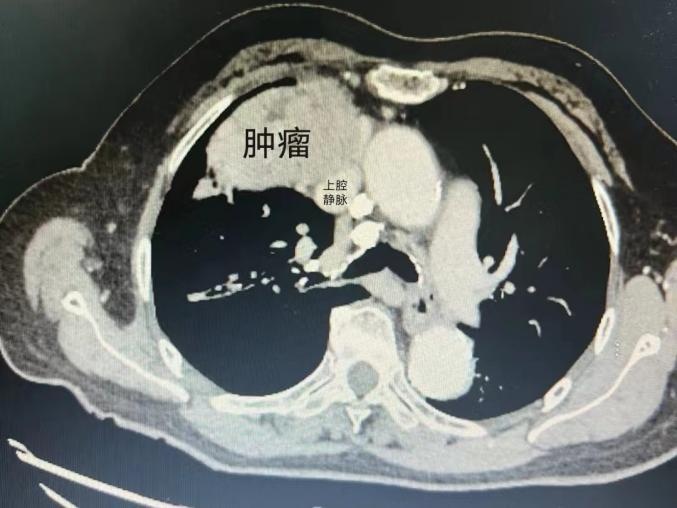

巨大的肿瘤几乎占据了80岁阿婆的整个右侧胸腔,最上端几乎延伸近颈部,而最外侧挤压着胸壁,心脏几乎被推至对侧胸腔……并且肿瘤已压迫周围大血管,与无名及上腔静脉(向心脏回流的重要血管)紧密排列,阿婆已经难以呼吸。

影像报告显示,肿瘤就像一块压在胸腔的大石头,让阿婆的右上肺完全压瘪不张,致使气管移位,导致老人气喘和刺激性咳嗽不断,简单测算一下,肿瘤的直径有10余公分,相当于一个小足球的大小。